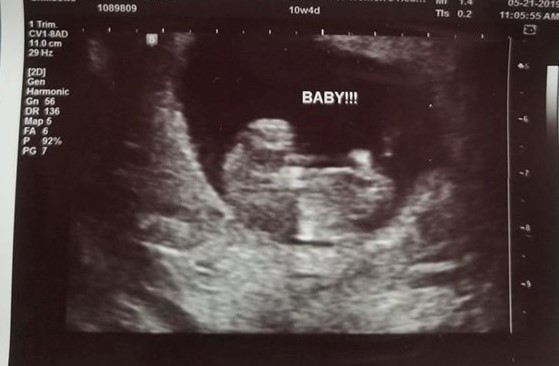

First Ultrasound – Reality!

I found out I was pregnant after taking 2 home tests then verifying with a blood test at my hematologist office the next day. I had to wait 10 days to see my OBGYN because I was already booked to travel for 8 days. In my last entry, Oh, Baby., I shared that I had… Continue reading First Ultrasound – Reality!